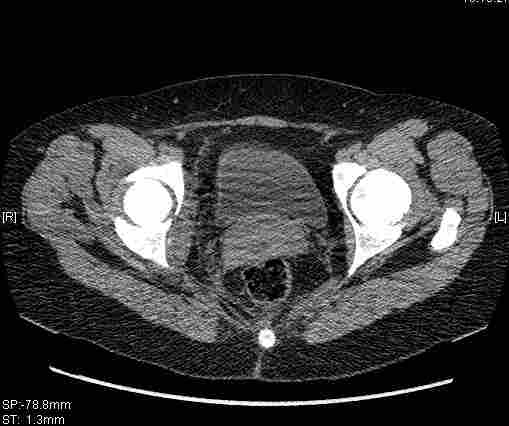

[Ortho] [1/2] Re: Т-образный перелом вертлужной впадины

Удалось сегодня вывести пациентку в соседнюю больницу, где есть кт.

Срезы сделаны  только горизонтальные.